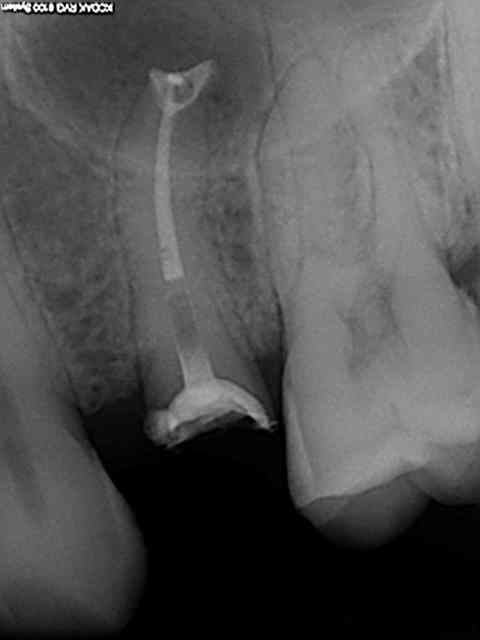

vous en pensez quoi de cette endo?

bonjour

j'ai fais cette endo mardi dernier,la dent etait assez difficile (canaux fins++,4 canaux)

la patiente ressentait une douleur dans le canal disto vestibulaire,(malgré troncu+intra-septale)

je n'ai pas réussi à aller plus loin d'ailleurs sur ce canal.

je ne suis pas super satisfaite au niveau radio sachant que je doit couronner.

en plus c'etait avec le reciproc que j'utilisait pour la 1ère fois.

j'y ai passée beaucoup trop de temps déjà(plus d'une heure)

que feriez vous?

couronne d'emblée ou reprise de certain canaux la prochaine fois?